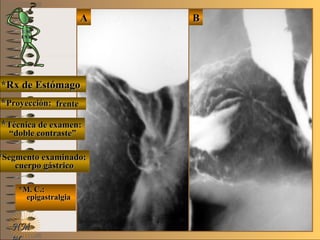

*Rx de Estómago*Rx de Estómago

**Proyección:Proyección:

**Técnica de examen:Técnica de examen:

**Segmento examinado:Segmento examinado:

*M. C.:*M. C.:

epigastralgiaepigastralgia

melenamelena

NMNM

detalledetalle

frentefrente

““doble contraste”doble contraste”

antro gástricoantro gástrico

A-A-El examen es normal o patológico?El examen es normal o patológico?

Examen patológico de estómago con técnica deExamen patológico de estómago con técnica de

doble contraste en proyección de frentedoble contraste en proyección de frente

B-B-La patología es congénita o adquirida?La patología es congénita o adquirida?

Patología adquiridaPatología adquirida

C-C- Dicha patología es orgánica, funcional o mixta?Dicha patología es orgánica, funcional o mixta?

**OpciónOpción

de volverde volver

a ver lasa ver las

imágenesimágenes

Patología adquirida orgánicaPatología adquirida orgánica

D-D-La misma es neoplásica o no neoplásica?La misma es neoplásica o no neoplásica?

Patología adquirida orgánica no neoplásicaPatología adquirida orgánica no neoplásica

E-E-Puede describir la o las imágenes patológicas?Puede describir la o las imágenes patológicas?

Se identifican en antro gástrico múltiplesSe identifican en antro gástrico múltiples imáge-imáge-

nes mixtasnes mixtas UNTUNT : elevado (inflamación) y: elevado (inflamación) y

deprimidas (erosión) focales compatibles condeprimidas (erosión) focales compatibles con

una gastritis madura completauna gastritis madura completa

**Opción avanzada para volver a ver las imágenes con reparosOpción avanzada para volver a ver las imágenes con reparos